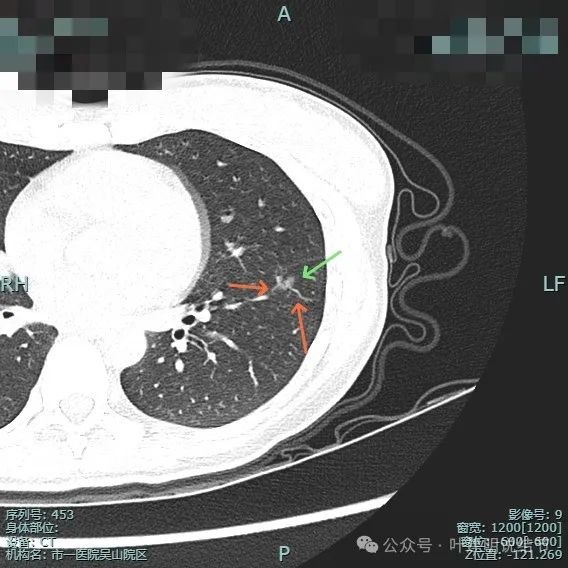

右侧病灶15:

病灶密度仍纯但不太均匀,整体轮廓与瘤肺边界清。

有小血管进入与类反晕征。

血管进入以及轮廓与边界清楚。

密度不均显杂乱。